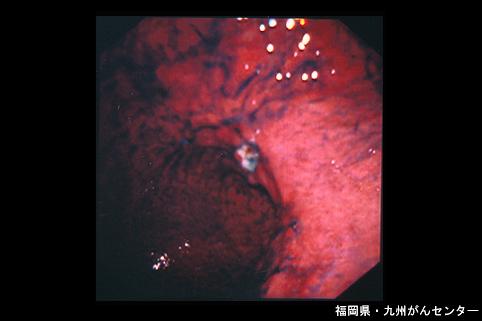

疾病(病理主体)的分类恶性上皮性肿瘤/腺癌

部位(按器官分)胃(部位)/胃角

检查方法内窥镜

肿瘤的肉眼分类0型(表在型)/IIc型(IIc+III)

肿瘤最大直径40以上

肿瘤的深度sm